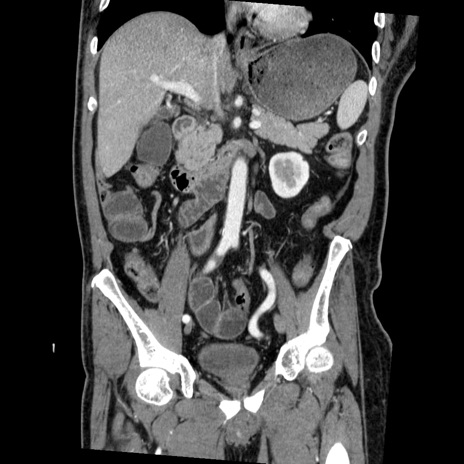

症例22(冠状断像)

【症例】50歳代男性

【主訴】腹痛

【現病歴】AVMからの被殻出血のため回復期リハ病棟入院中。 本日午後3時頃急に下腹部痛が出現した。

【既往歴】AVM、被殻出血、虫垂炎、高血圧

【身体所見】意識晴明、左半身不全麻痺、会話の理解は良好、36.5°C、腹部:膨隆、全体に板状硬、下腹部正中に圧痛点あり、反跳痛-、筋性防御不明、右下腹部にope scar

【データ】WBC 9400、CRP 0.06